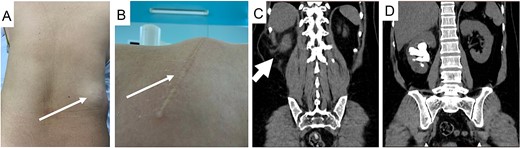

Baseline preoperative laboratory tests were normal. A lateral flank position mini PCNL was performed using combined US and flouroscopy guidance for renal puncture (Fig. 4A). After 35 min of lithotripsy, the stone burden was successfully removed, and the patient was discharged after 3 days without any complications. He declined treatment for his lumbar bulge after considering the risks associated with another operation.

Real-time US guide for renal puncture (A), mini PCNL with lateral position (B), and nephrostomy after completing stone clearance (C).